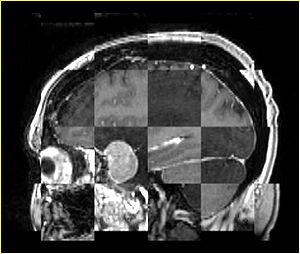

• Checkerboard appearance of unregistered images for the representative data of interest

• Case03